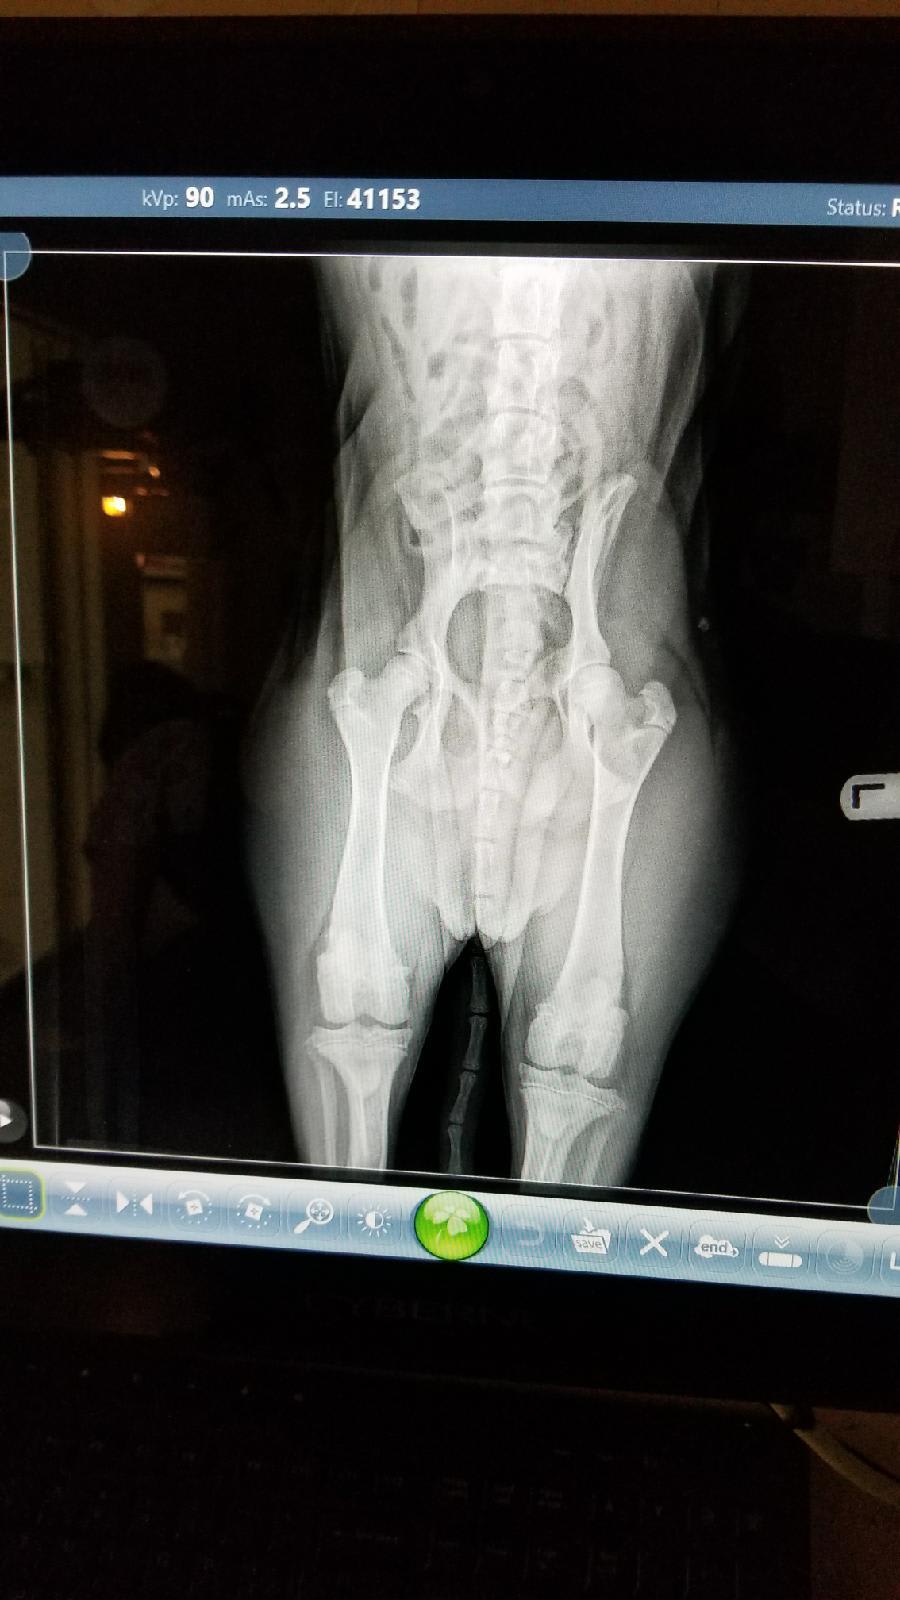

Does my young dog's hip X-ray look normal despite appearing uneven?

Pet's info: Dog | Mixed Breed Large (61lb +) | Female | unspayed | 8 months and 8 days old | 39 lbs

Does this hip X-ray look problematic. I’m curious because they look different.

This hip X-ray looks normal. She is not absolutely square so each side doesn’t look even. She’s a young dog so the bones are not fully calcified so that also makes it look like there may be a fracture but there is not one. I like the angle of the head of the femur and it’s seated fairly well into the socket. If she has hip pain it can be from bone inflammation or a ligament problem also. Thanks for using Petco Pet Education Center, formerly Petcoach to help you care for Ruthie.